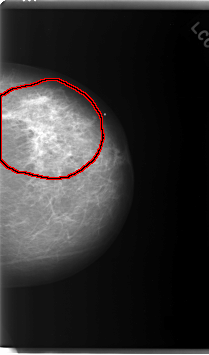

C_0081_1.LEFT_CC

LEFT_CC LINES 6032 PIXELS_PER_LINE 3544 BITS_PER_PIXEL 12 RESOLUTION 50 OVERLAY

FILE: C_0081_1.LEFT_CC.OVERLAY

TOTAL_ABNORMALITIES 1

ABNORMALITY 1

LESION_TYPE MASS SHAPE IRREGULAR MARGINS SPICULATED

ASSESSMENT 5

SUBTLETY 4

PATHOLOGY MALIGNANT

TOTAL_OUTLINES 1

BOUNDARY